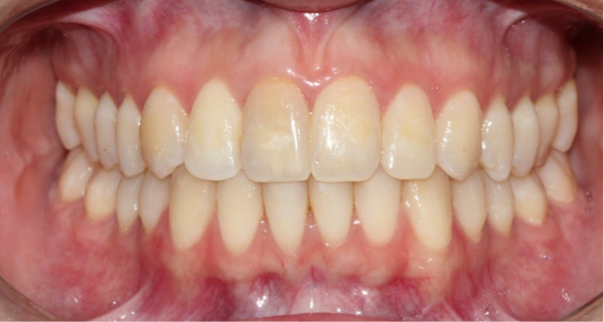

Tooth Injury comprises a group of clinical conditions that can have the separation or breakage of the tooth and its surrounding tissues. A case of multiple concomitant dental trauma is reported. In 2004, a female patient, 11 years old, visited the dental office a half hour after a dental trauma caused by a fall in the pool. She complained of mild discomfort in the tooth 11; in a clinical analysis, it was partially displaced from its socket and showed grade 2 mobility; in a radiographic analysis, the tooth showed an increase in the periodontal ligament space, a diagnosis of extrusive luxation. The adjacent teeth 21 and 22, presented subgingival bleeding, diagnosed with subluxation. After preparing the treatment plan, clinical approach consisted of manual reduction of the tooth 11 and non-rigid splint of affected teeth. The patient received a prescription of antibiotic and anti-inflammatory. After 15 days, the splint was removed and the teeth 11, 21 and 22 showed pulpal sensibility, maintaining the same results for 4 months. In the 4th month, tooth 11 was diagnosed with pulp necrosis, thus requiring endodontic treatment. After 10 years, teeth were asymptomatic, with a slight color change in tooth 11; the cone beam scan indicated root resorption in the apical third of the three elements and the presence of dystrophic calcification of teeth 21 and 22. In conclusion, the injured teeth remain in function with relevant follow-up period, highlighting the search for a response, upon the purpose of the study.